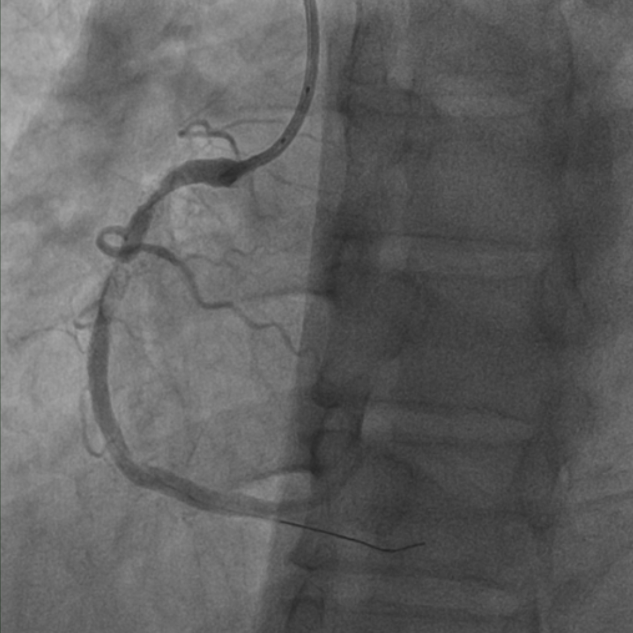

抽吸【例】量|【李】解抽吸患者获益